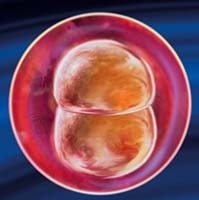

Розмір ембріона в цей час становить усього лише 0,15 міліметрів. Поки ваш малюк являє собою скупчення клітин, як показано на фото на 3 тижні вагітності. Продовжуючи збільшуватися в розмірах, зародок прагнути до матки по маткових трубах.

Саме зачаття і запліднення відбуваються на 2 акушерської тижня. 3 тиждень - це початок життя вашої дитини. Малюк ще дуже маленький, схожий на мініатюрну вушну раковину і його довжина складає всього 4 мм.